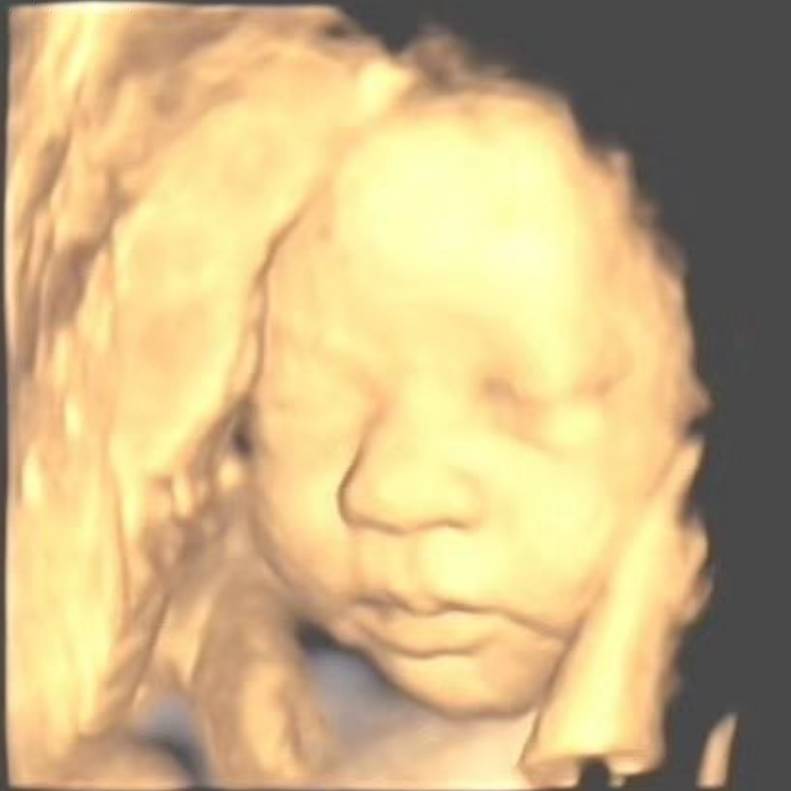

做好孕前检查和产前筛查……预防出生缺陷

据相关统计数据显示,我国每年新增的出生缺陷儿大约90万,平均每30秒就出生一个有缺陷的新生儿,占每年出生人口总数的4%~6%,

第11个唐氏综合征日《重视唐氏筛查 孕育健康宝宝》

2022年3月21日是第11个“世界唐氏综合征日”,活动主题是“重视唐氏筛查,孕育健康宝宝”,旨在提高全社会对唐氏综合征的认识和关

避免生“兔唇”宝宝,孕妈妈得这么做~

唇裂,这是一种发病率约为1/700的多基因疾病,它包括单纯唇裂和唇腭裂,就是我们俗称的“兔唇”。避免怀有先天缺陷的“兔唇”宝宝